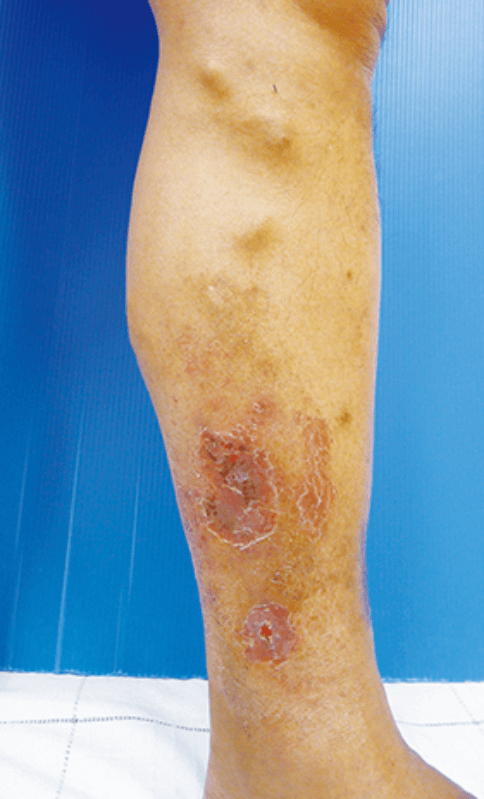

静脈瘤などによって下肢の静脈がうっ血した状態が長く(通常1年以上)続くと、慢性的な下肢静脈の循環障害に伴う、様々な症状がでてきます。これらをまとめて〝下肢静脈うっ滞症候群〟とよびます。静脈瘤が進行するとうっ滞症候群を合併することが珍しくありません。その症状として以下のようなものがあります。

②皮膚炎、湿疹

皮膚炎や湿疹を起こしやすくなります。静脈瘤の真上や足首にできやすく、皮膚がカサカサして表皮がむけたり、滲出液でジュクジュクしたりすることもあります。皮膚・皮下組織の栄養障害や炎症の繰り返しにより、皮下組織・皮下脂肪が板のように硬くなることもあります。

④色素沈着

静脈が拡張し、皮膚が弱くなっているため、掻いたり、少しの打撲によって皮下出血しやすくなります。出血すると血液の成分が組織に漏れ出ます。血液にはヘモジデリンと呼ばれる鉄を成分とする色素が含まれており、これらが組織内に沈着することによって、皮膚は、茶褐色や黒褐色を呈するようになります。